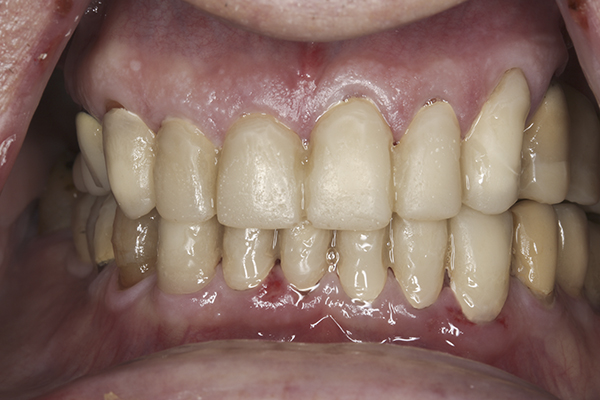

(32.) Postoperative right lateral, open view.

Figure 32

(35.) Postoperative right lateral, closed view.

Figure 35